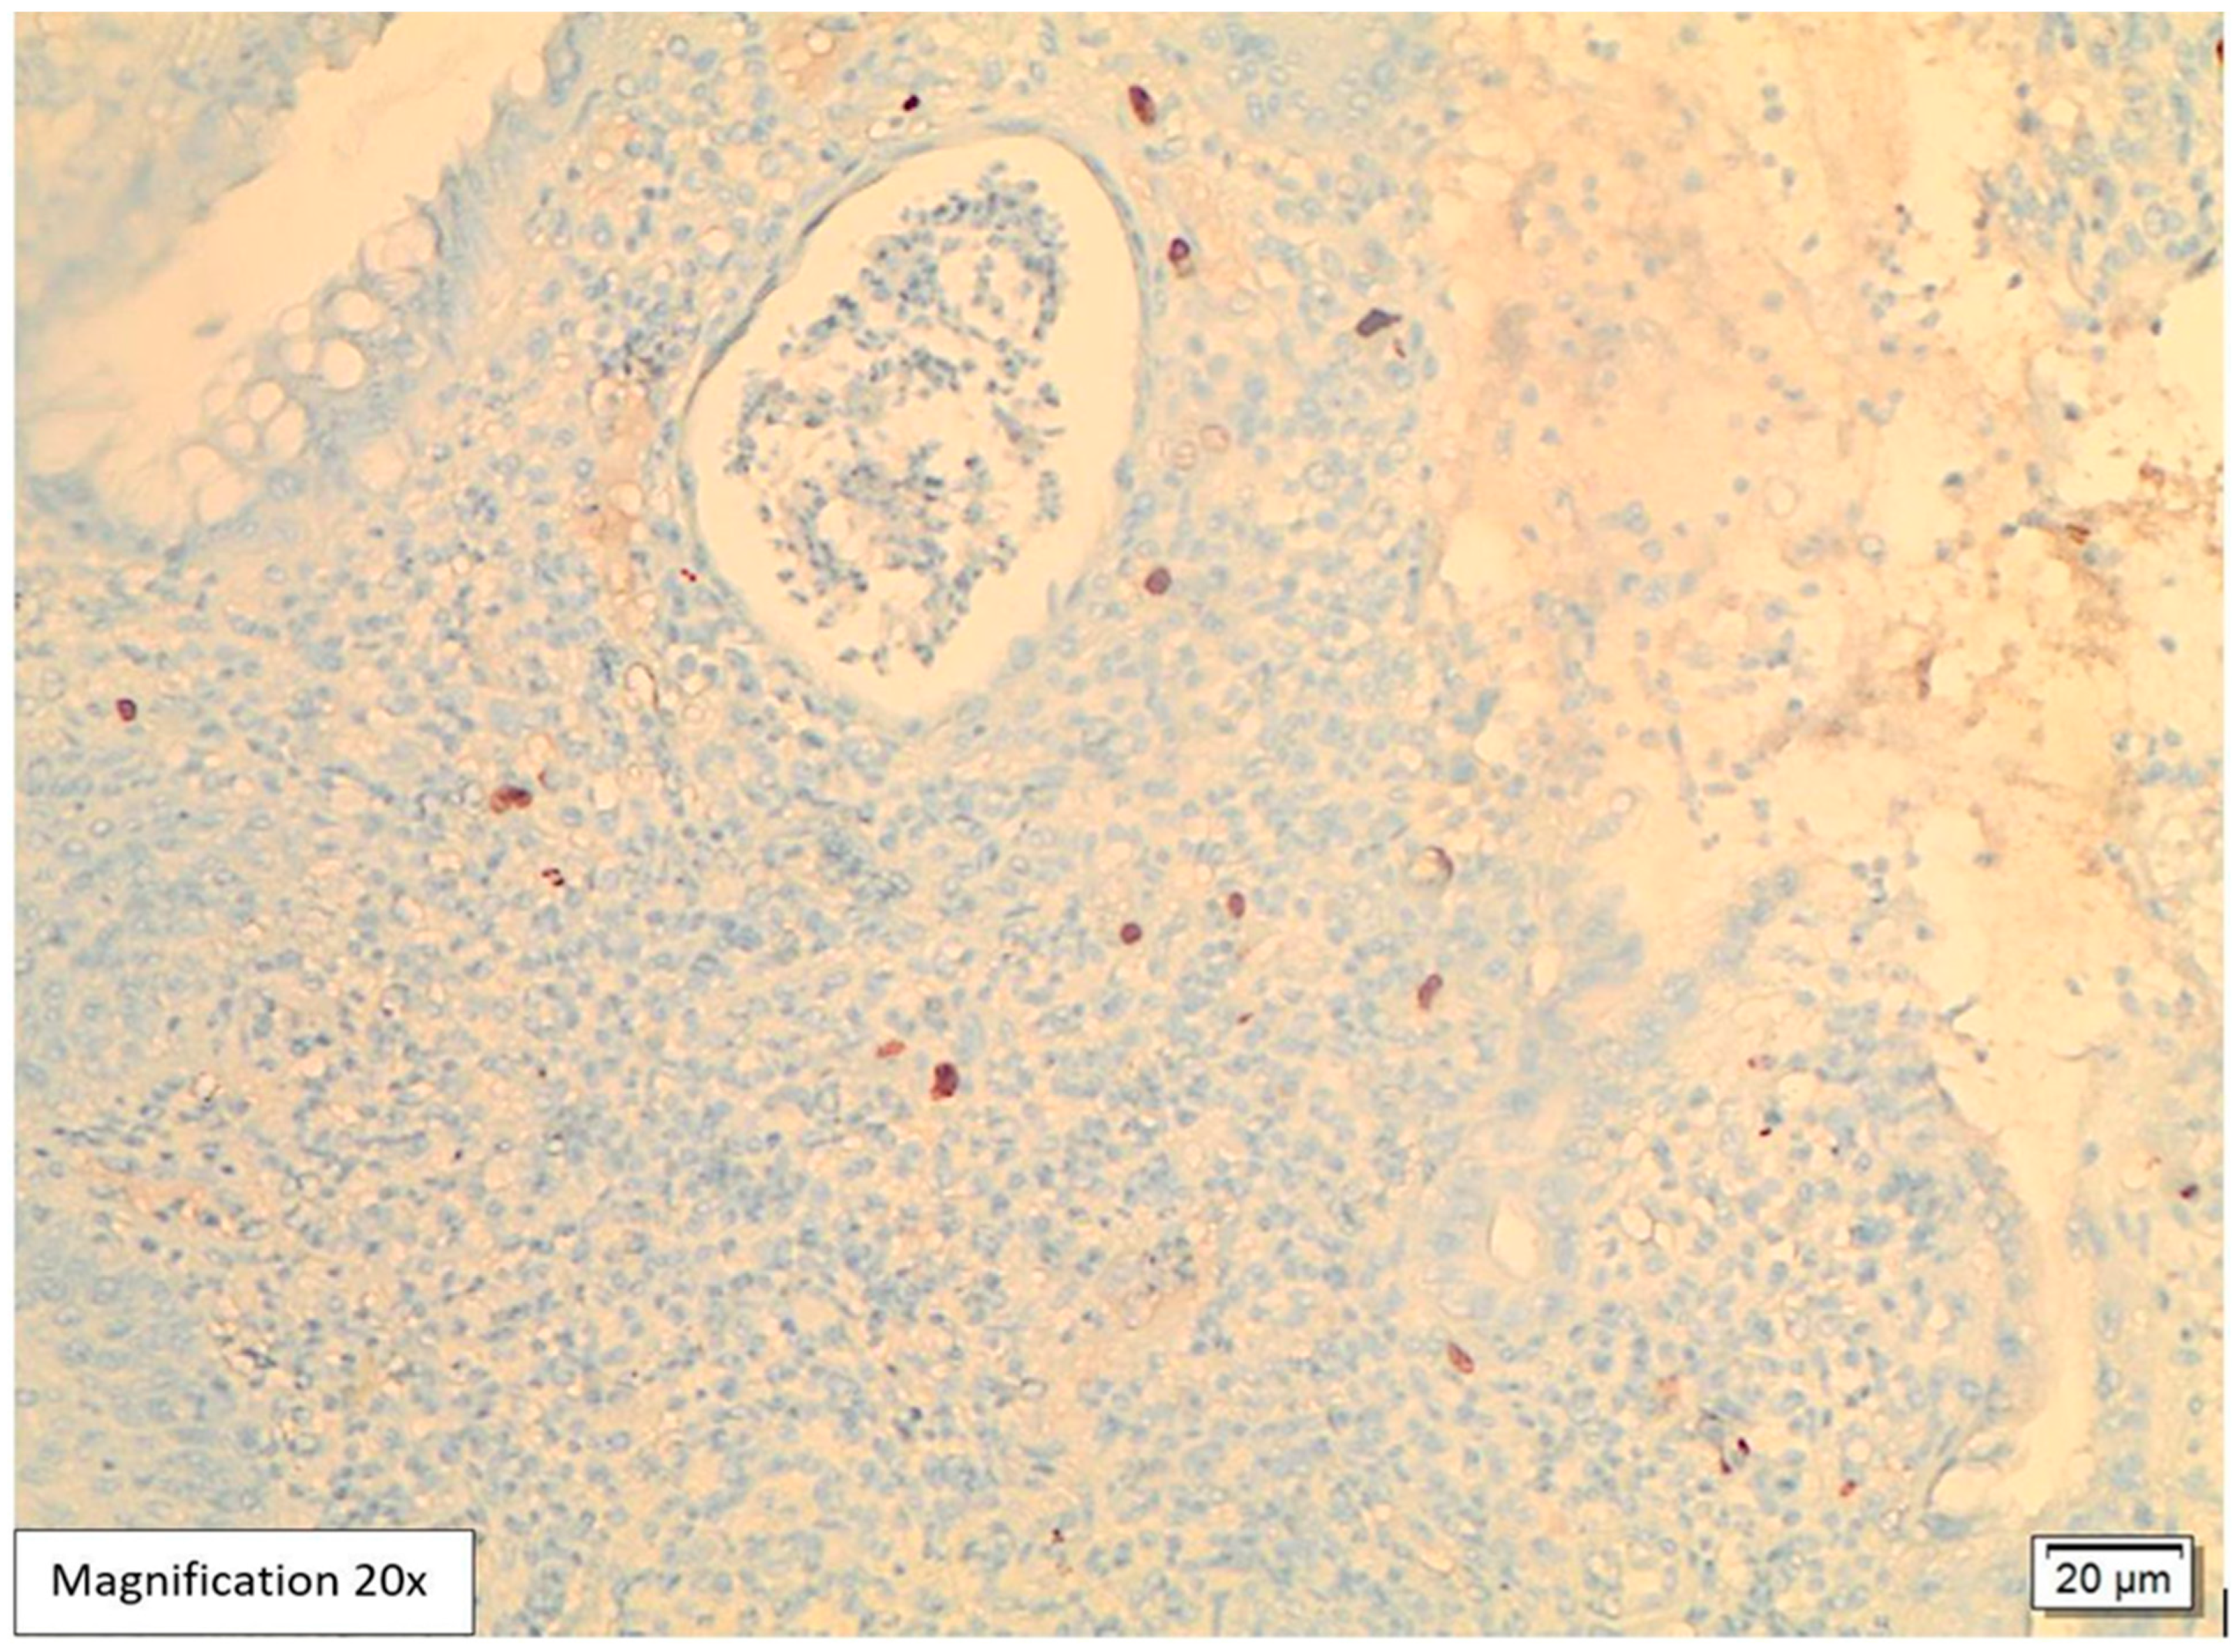

Case Presentation